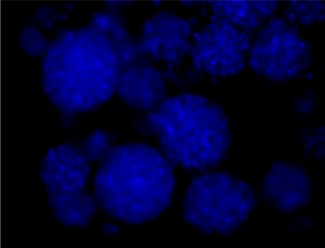

Immunofluorescence staining of Src and Phospho-Src

P-SRC Tyr416

Antibo​dy